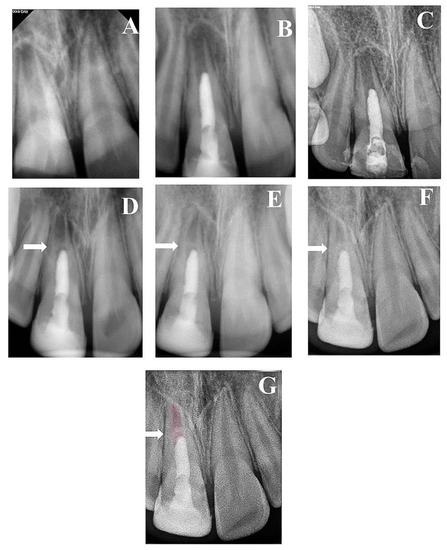

| 1 | Male | 9 | 11 | Trauma | 11.088 | 0.405 | 0.63 | 2 years | No lesion | NA |

| 2 | Male | 9 | 21 | Trauma | 10.48 | 0.477 | 1.021 | 3 years | 6 | No respond |

| 3 | Male | 9 | 11 | Trauma | 12.562 | 0.584 | 1.53 | 3 years | 6 | Respond |

| 4 | Male | 9 | 21 | Trauma | 12.36 | 0.44 | 1.1 | 3 years | 6 | Respond |

| 5 | Male | 10 | 11 | Trauma | 14.014 | 0.81 | 0.92 | 3 years | 6 | No respond |

| 6 | Male | 11 | 21 | Trauma | 14.38 | 0.78 | 0.9 | 2 years | 6 | NA |

| 7 | Female | 8 | 21 | Trauma | 10.01 | 0.36 | 1.02 | 3 years | 6 | No respond |

| 8 | Female | 8 | 47 | Caries | 10.51 | 0.41 | 1.28 | 2 years | 9 | NA |

| Preoperative | 10.36 | 1.14 | 0.48 |

| 6th Month | 10.47 | 1.15 | 0.72 |

| 12th Month | 10.64 | 1.28 | 0.74 |

| 2nd Year | 10.79 | 1.29 | 0.76 |

| 3rd Year | 10.92 | 0.65 | 0.86 |

| 8th Year | 11.4 | 0.24 | 0.98 |